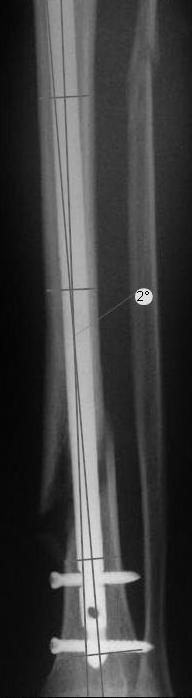

Вальгус, стержень в дистальный отломок введен не на оптимальную длину. Такой диастаз будет долго заполняться, что чревато переломом стержня по ближайшему отверстию.

Александр Николаевич! "а как Вы померили точные градусы вальгуса?", ",а сколько допустимо?, а насколько вальгус клинически значим?" Помоему на эти вопросы Вы всегда отвечали - если есть вальгус клинически, надо исправлять.

Вы бы стали оперировать или рекомендовали бы своему родственнику оперироваться из-за 2 градусов?

Все наши сомнения связаны с тем, что этих незначительных погрешностей (небольшой вальгус, неглубоко пробит гвоздь, мало запирающих винтов в

дистальном отломке) не одна, а несколько, и вместе они могут значительно осложнить дальнейшую жизнь пациенту. В нашей практике были подобные случаи, при которых после разрешения полной нагрузки либо начинала увеличиваться деформация, либо происходил перелом гвоздя по ближайшему отверстию. Кроме того, при диафизарных переломах, имея в арсенале надежный фиксатор, нет никакой необходимости вынуждать пациента ограничивать нагрузку на ногу в течении 2-3 месяцев.

Взвесив все <<за>> и <<против>>, мы приняли решение и выполнили реостеостинтез: выбили гвоздь до линии перелома, провели отклоняющую

спицу, забили обратно гвоздь и заблокировали внизу 3-мя винтами, вверху одним. Вся операция заняла меньше часа. Сегодня пациент ушел от нас домой с полной нагрузкой на ногу.